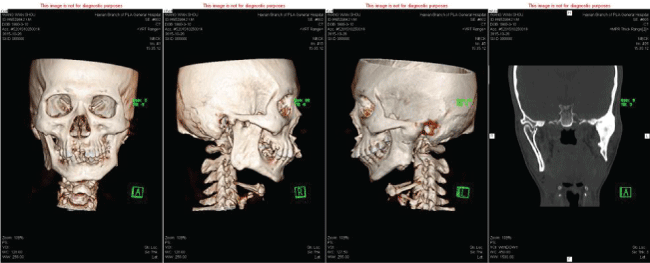

Man 35 years old. He fell from tree with the chin hitting on the ground at the age of nine, leading to the condylar fracture. In the rural area, people lack of conscious of doctor, so we have no idea about the treatment that he took at that time. After the trauma, he begun to unable to open his mouth, from 2 mm to complete limited mouth opening during 2 years. Now he came to doctor because he cannot open his mouth for 24 years. He is diagnosed as temporomandiblular joint ankylosis, with maxillofacial deformity, facial asymmetry, micrognathia, malocclusion, complete restriction of opening, bad oral hygiene (Figure 1). The CT scan shows the left TMJ is completely obliterated by bony ankylotic mass growing between the mandibular ramus and cranial base (Figure 2). The right side the head of the condylar process is visible but significantly deformed, with the fibrous adhesions making TMJ movement impossible (Figure 2). We designed a preauricular incision in order to expose the ankylosis compeletly with hidden beauty and advoid facial nerve damage, our operative protocol for the left TMJ ankylosis entailed resection of ankylotic mass, arthroplasty, interpositional tissue transfer to the TMJ with temporalis fascial flap, the right TMJ was dealed with fibrous tissue release and partly condylar head resection (Figure 3). After the surgery he can open his mouth to 25 mm.

Figure 2: CT Scan show the left TMJ bony ankylotic mass, the right condylar head dislocation and maxillofacial deformity.

View Figure 2